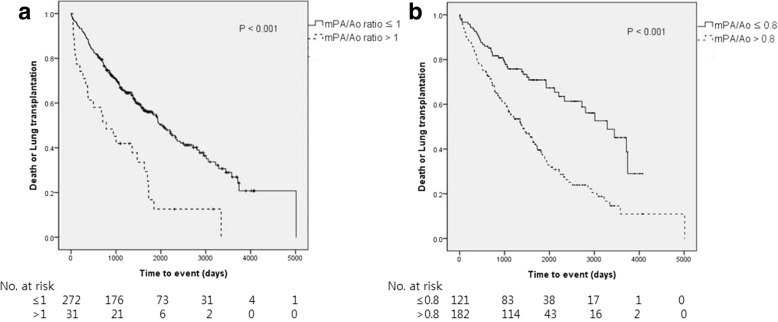

Kaplan-Meier analysis of time to death or lung transplantation revealed that patients with an mPA/Ao ratio > 1.0 had a worse outcome than those with an mPA/Ao ratio ≤ 1.0. Furthermore, the patients with an mPA/Ao ratio > 0.8 had a worse outcome than those with an mPA/Ao ratio ≤ 0.8 (P = .003; Fig. 2).

Fig. 2.

Kaplan-Meier analysis of time to death or lung transplantation in patients with idiopathic pulmonary fibrosis according to whether the ratio of the diameter of the main pulmonary artery to that of the aorta on chest computed tomography was a ≤1.0 or > 1 or b ≤0.8 or > 0.8 (P < .001)